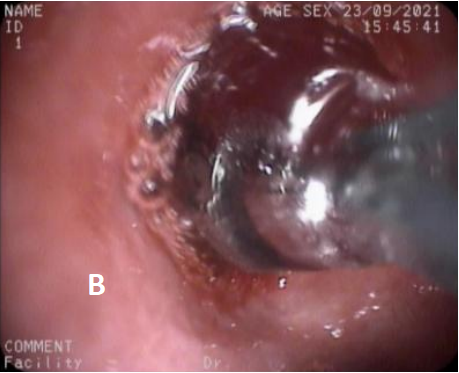

图5 第3次治疗(冷冻治疗+球囊扩张2021/9/23)

A. 冷冻治疗 B. 球囊扩张